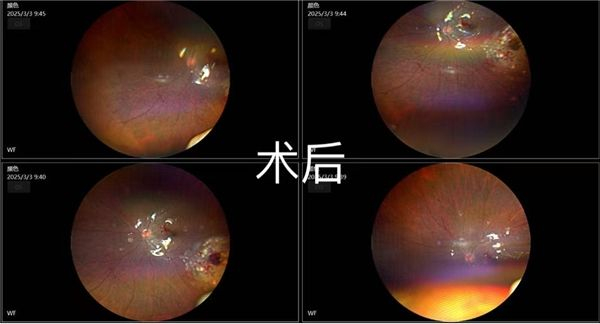

眼看病情紧急,普瑞眼科第一时间安排“视网膜脱离就诊绿色通道”,为诚诚进行了全面的眼科检查,包括眼部B超、视野检查、眼底超广角照相等,以便全方位掌握孩子的眼底状况,尽快安排手术,助其摆脱失明之险。

诚诚的主刀医师古世才主任看到检查报告后,与团队迅速制定了详尽的治疗方案——结合孩子视网膜脱离的部位、脱离的范围大小、身体情况以及后续恢复等各方面综合考量,制定了“左眼后入路玻璃体切割术+视网膜脱离复位术+视网膜激光光凝+硅油填充”的手术方案。

最终,在团队的紧密配合下,诚诚的手术顺利完成。术后复查,诚诚的视网膜复位情况良好。看着诚诚左眼得以保住,孩子父母悬着的心总算落地,并对医护人员表达了感激之情。